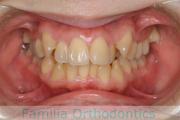

No.22V-244

- 主な症状:

- 上顎前突

- その他の症状:

- 叢生

- 年齢:

- 14歳

- 性別:

- 女性

- 抜歯部位

- 上:

- 44

- 下:

- 8558

- 主な使用装置:

- FEA

- 治療にかかった費用:

- 88万円

上の前歯を治したいとのことで来院されました。かなり強い前歯の突出がありましたので、上下左右から小臼歯を抜歯して、マルチブラケット法を行いました。約2年半、30回程度の通院が必要でした。前歯の移動量が多い上顎前突(出っ歯)の治療は、前歯の歯根吸収のリスクが特に高めです。